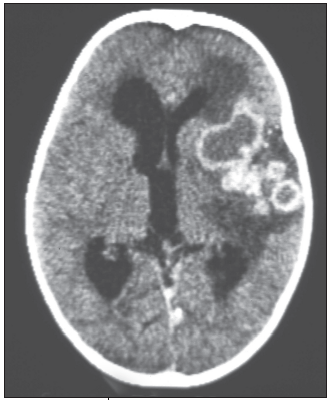

Tuberculomas, on the other hand, are typically associated with a strong tuberculin skin test response. They present clinically as local mass lesions with focal neurologic deficits representing the site of disease (Figure 11). They may also evolve during the treatment of miliary TB or tuberculous meningitis as the immune system recovers.